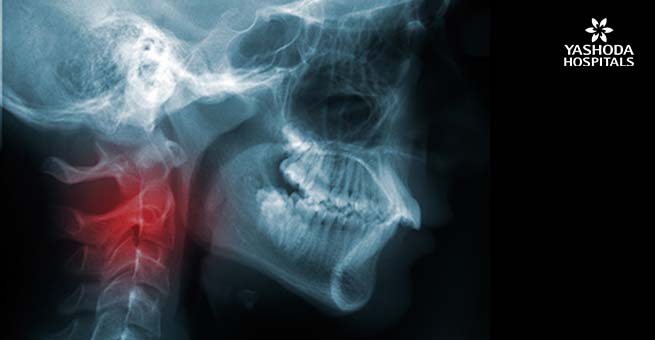

Diagnosis and Treatment for Head and Neck cancers

How is head and neck cancer diagnosed?

Head and neck cancer diagnosis is made by various tests and images that are necessary to establish an accurate diagnosis, and they are

- X rays.